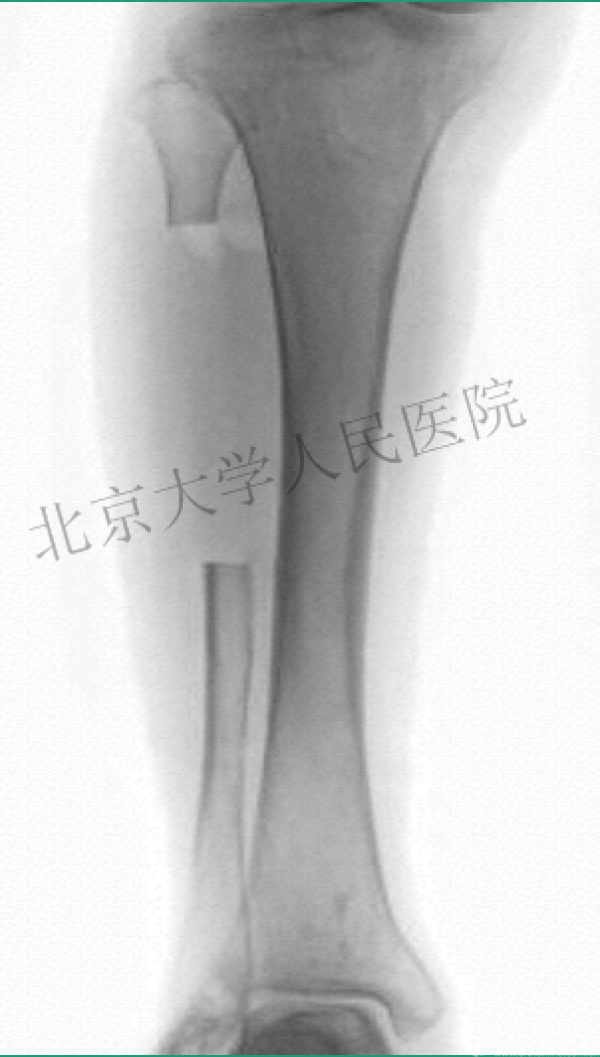

X射线照射后

10天后

值得吗?